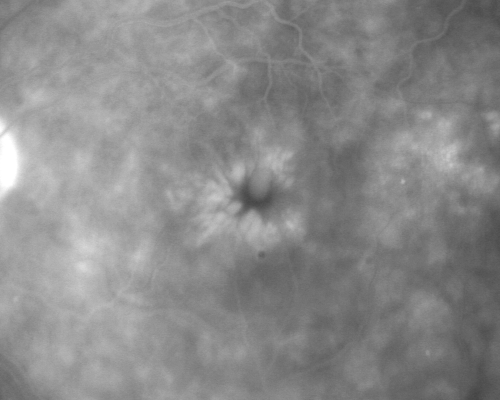

Chronic Pseudophakic Cystoid Macular Edema in a Patient with Diabetes

74-year-old woman has chronic cystoid macular edema in the left eye.  She has had vision loss intermittently in that eye for 2 years, the right eye, unfortunately, lost vision from a central retinal vein occlusion in 6 years ago.